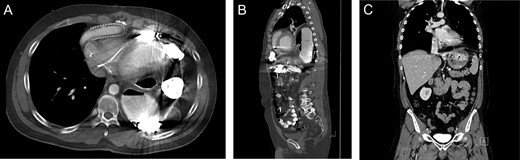

Patient #1 is a 60-year-old male with a history of gastroesophageal reflux disease and ischemic cardiomyopathy. He underwent placement of a Heartmate II LVAD in 2013 before undergoing an orthotopic heart transplant (OHT) 2 months later. After an initially uncomplicated course, he presented to the emergency department 1 year following transplant with reflux, epigastric pain and a recent 10-pound weight loss. Prior endoscopic evaluations had been normal; however, a chest X-ray was suggestive of intrathoracic bowel. A subsequent CT scan demonstrated an intrapericardial hernia containing the transverse colon (Fig. 1A–D) and the patient was taken to the operating room for a robotic diaphragmatic hernia repair.

Imaging from Case #1. (A) Preoperative X-ray demonstrating loop of bowel in the thoracic cavity. (B) Preoperative CT scan, saggital view of diaphragmatic defect. (C) Preoperative CT scan, coronal view demonstrating colon passing through diaphragmatic defect. (D) Preoperative CT scan, axial view demonstrating intrapericardial transverse colon. (E) Postoperative X-ray demonstrating reduction of hernia contents.